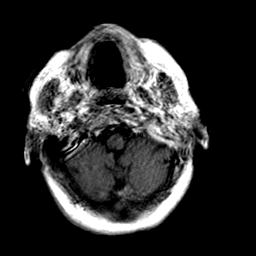

Creutzfeld-Jakob disease: gadolinium enchanced T1-Weighted MR -- Slice #2

[Home][Help][Clinical] Slice 2